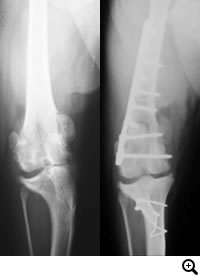

膝蓋骨脱臼グレード4

症状:グレード4になると、重度の跛行を呈することが多くなります。

膝蓋骨脱臼グレード4とは

成長期に膝蓋骨が大腿骨遠位にある滑車溝から脱臼し、大腿骨や脛骨の変形が急速に進行し、膝蓋骨が脱臼し固定されている状態。指で脱臼をなおそうとしても戻らない状態。

触診、レントゲン検査

治療

外科手術が適応であれば、Block Resectionによる造溝術と脛骨粗面転移術に加え、必要に応じて変形した大腿骨を矯正する骨切り術を同時におこない、膝蓋骨が正しい位置におさまるようアライメントをただします。